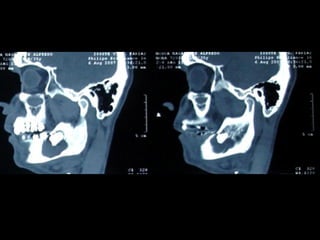

En el estudio radiográfico determinamos que el factor causal fué un foco séptico

dentario a nivel de segundo molar inferior izquierdo.

Después de 14 días de hospitalización la paciente es egresada con un mejor

pronóstico. Habiendo drenado compartimientos aponeuróticos.

En esta imagen pueden apreciar

como la infección además de

fibrosis muscular ha determinado

lesión del nervio facial. Por lo que

se envía a fisioterapia.